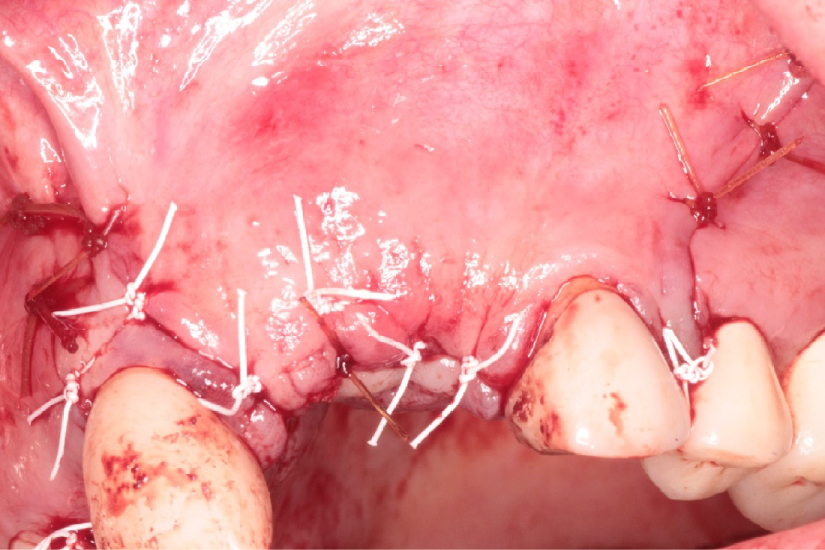

The patient received 2 gm of amoxicillin as an antibiotic prophylaxis (Zimox, Pfizer Inc., USA). Intravenous sedation was administered and approximately 30 cc of venous blood was drawn in order to prepare 3-5 cc of platelet rich fibrin (PRF). 2% Lidocaine HCL 1:100, 000 with epinephrine (Septodont Cook-Waite, Lancaster, PA, USA) was used for local infiltration at the #s 6-11 sites. Both surgical sites were prepared in the same manner. Bilateral papilla sparing incisions were completed (Figure 4 and Figure 5). Once the labial or buccal aspects were exposed, a #7011 bur was used to perforate the bone and establish bleeding bone (Figure 6 and Figure 7). At both sites, a Cytoplast® Ti-250 (Osteogenics Biomedical, Lubbock, TX, USA) titanium reinforced membrane shaped and sized to cover the proposed GBR sites and allow space for the bone regeneration to occur. The membrane each were secured with bone tacks first at the vestibule (Tru Tack® ACE Boston, MA, USA) (Figure 8). Then MinerOss® bone graft (Biohorizons, Birmingham, AL, USA) was placed at both surgical sites (Figures 9 and Figure 10) followed by a single superior membrane bone tack (Figures 11 and Figure 12). PRF was placed over the membranes (Figures 13 and Figure 14) and the surgical flaps were repositioned without tension with Cytoplast® and chromic sutures (Figures 15 and Figure 16).

Figure 15: Flap repositioned without tension using Cytoplast® and chromic sutures at the #7 site. View Figure 15

Figure 16: Flap repositioned without tension using Cytoplast® and chromic sutures at the #s 9 and 10 sites. View Figure 16